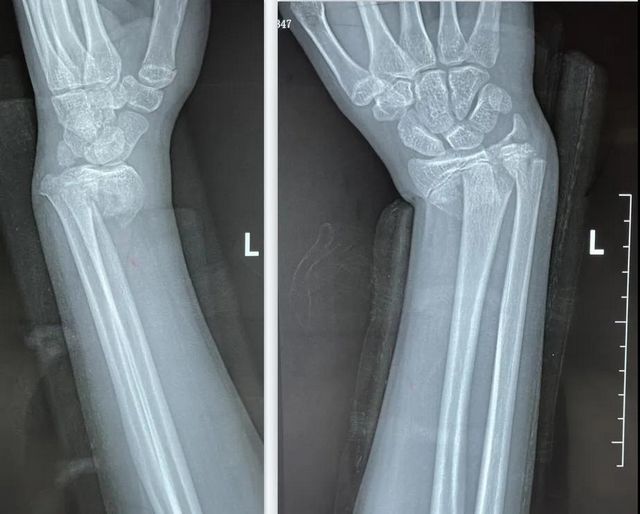

突然,涛涛脚下一滑,左臂重重着地,疼得大叫起来。老师赶紧联系了涛涛妈妈,同时将涛涛送往医院救治,诊断为左尺骨远端骨折伴桡骨远端骨折。

急诊科医生接诊后,立即通知了贺智榆。贺智榆在有条不紊地处理完涛涛的骨折后,又赶紧为小林诊治,小林被诊断为左手尺桡骨骨折。

21:00,又来了一位可爱的小姑娘珊珊(化名)。11岁的珊珊在家玩耍时不慎摔倒,左手着地,当即感觉左腕关节疼痛,珊珊妈妈立马将她送往医院救治,被诊断为左桡骨远端骨折。